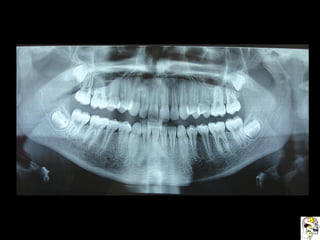

Se observa el número total de órganos dentarios incluyendo

terceros molares.

No hay tratamiento de conductos radiculares

Buen trabeculado óseo de tipo I

Se observa elnúmero total de órganos dentarios incluyendo terceros molares. No hay tratamiento de conductos radiculares Buen trabeculado óseo de tipo I Se observa el número total de órganos dentarios incluyendo terceros molares. No hay tratamiento de conductos radiculares Buen trabeculado óseo de tipo I